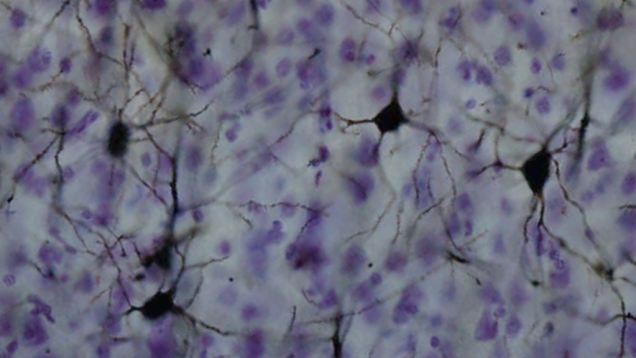

Scientists have uncovered a new kind of electrical process in the human brain that could play a key role in the unique way our brains compute.